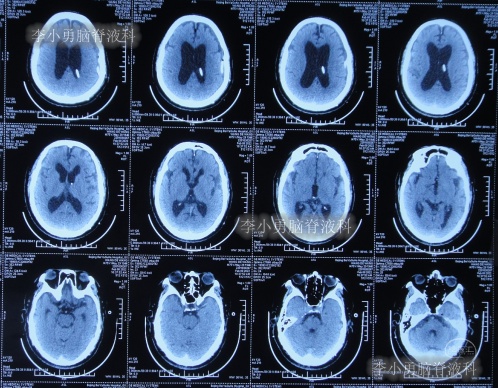

2021年4月14日(腰大池腹腔分流术后17天),头痛腿沉再次加重,复查头部CT示硬膜下血肿(图-3)。

图-3:2021年4月14日头部CT